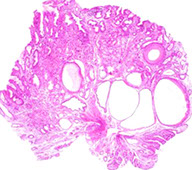

Gastritis cystica polyposa / profunda

uncommon, usually at gastroenterostomy stomas; a form of mucosal prolapse, c multiple polyps forming a circular ring, c thickened mucosal layer and lots of submucosal microcysts

Micro: elongated pits c serration, hyperplasia, custic dilation of pyloric glands that herniate into submucosa c regenerative surface epithelial change and fundic gland loss

- disorganized strands of muscularis mucosa in irregular bundles

Gastritis cystica profunda   https://openi.nlm.nih.gov/detailedresult.php?img=PMC2893317_kjr-11-457-g009&req=4